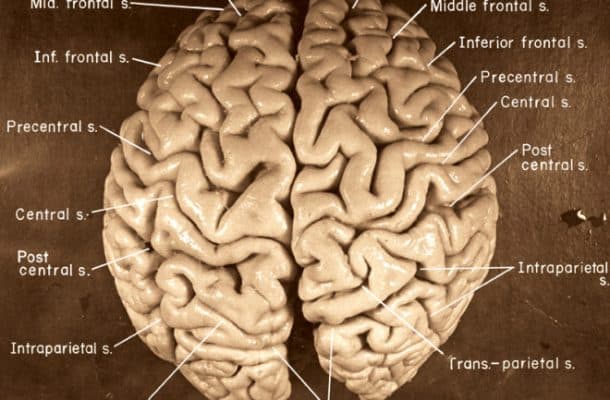

Ανθρώπινος εγκέφαλος